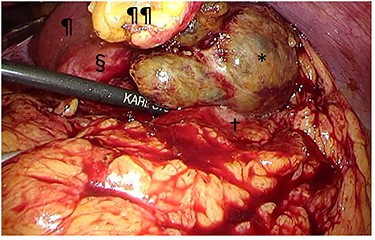

A 56-year-old woman presented to another hospital with acute abdomen. Computed tomography (CT) examination demonstrated a tumor 10 cm in diameter that protruded from the left lateral segment of the liver, with evidence suggestive of rupture of the liver tumor (Fig. 1). Since the patient was in good general condition, she was referred to our hospital for further evaluation. Her blood biochemical parameters when she was referred to our hospital were hemoglobin: 11.6 g/dl, albumin: 3.4 g/dl, γ-globulin: 18.5% and anti-acetylcholine receptor antibody: <0.3 nmol/L. Dynamic CT presented a liver tumor 10 cm in diameter, which was located at the left lateral segment of the liver, with a clear margin. A mass with an irregular margin was also identified in the anterior mediastinum (Fig. 2). On percutaneous angiography, since obvious extravasation of the contrast medium could not be identified, the arteries of the left lateral segment were embolized to prevent re-bleeding. Although a definitive preoperative diagnosis could not be made using magnetic resonance imaging (MRI) (Fig. 3), fluorodeoxyglucose positron emission tomography (FDG) showed increased FDG uptake in both the hepatic and anterior mediastinal tumors (Fig. 4). Although the liver tumor was suspected to be metastasis secondary to a thymoma based on the clinical findings, percutaneous tumor biopsy was performed to confirm the pathological diagnosis. The biopsy suggested malignant T-cell lymphoma or metastatic thymoma. In order to prevent re-rupture of the hepatic tumor, to confirm the pathological diagnosis and to potentially achieve a curative resection, the patient underwent laparoscopic left lateral segmentectomy (Fig. 5). Although the tumor was found to be adherent to the stomach, blunt dissection was possible. In addition, no peritoneal dissemination was detected. The surgical duration was 212 min and estimated blood loss was 50 ml. The liver tumor was pathologically diagnosed as metastatic thymoma type AB (Fig. 6). The patient’s postoperative course was uneventful and she subsequently underwent radical thymectomy 3 months after the liver resection. The thymic tumor was pathologically diagnosed as thymoma type B2. Currently, 30 months after thymectomy, she remains free from tumor recurrence.

Intraoperative findings. The tumor (§) with its protruding content (*) was adherent to the greater omentum and stomach (†). The tumor was bluntly dissected and no peritoneal dissemination was observed. ¶liver; ¶¶divided round ligament.